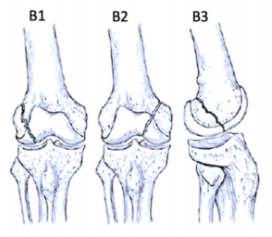

股骨遠端骨折分型

股骨遠端骨折可根據骨折模式、部位和膝關節受累情況進行分型 ,AO/OTA分型常用于對這些骨折進行分類。在每個類別中,骨折可根據復雜性和移位程度進一步分類,對于與全膝關節置換術(TKA)相關的假體周圍股骨遠端骨折,基于骨折移位和TKA股骨假體完整性的Lewis和Rorabeck分型(1997年)是最常用的分型:

A型:關節外骨折

不累及關節面

B型:部分關節內骨折

累及部分關節面但保持一定的關節匹配性

C型:完全關節內骨折

關節面完全破壞